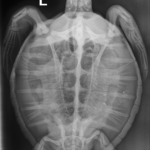

10.7 lbs. non -FP juvenile green

Severe abrasions to head and flippers, moderate abrasions on carapace and plastron. old wound on upper right side of carapace